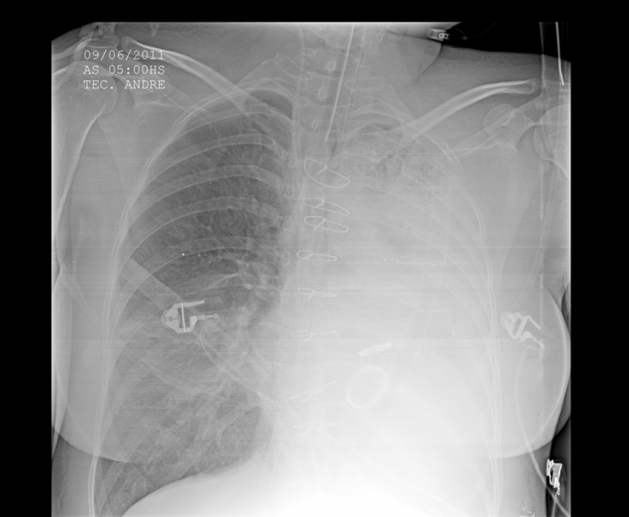

A 58 year old male with a history of HTN, HLD, and a 45 pack-year smoking history presents to the hospital in respiratory distress. He is holding an emesis bag filled with bright red blood. Using suctioning and a bougie, you successfully intubate him and obtain the below portable chest x-ray. What is the next best step to take in the management of this patient?

Answer: B. This patient is presenting with massive hemoptysis likely due to underlying malignancy. Massive hemoptysis is defined as >100 mL of blood loss in 1 hour or 1,000 mL of blood in 24 hours. Management of the airway is the most important first step, and the patient should be intubated with a 8.0 endotracheal tube if possible to prepare for future bronchoscopy. In order to keep blood from spreading to the unaffected lung, the patient’s lung that is bleeding should be placed down (in this case, the patient’s left lung is bleeding, therefore he is placed in the left lateral decubitus position). Selective intubation of a bronchus should be directed towards the unaffected lung to improve oxygenation to that side. In this case, the patient’s non-bleeding lung was the right side, therefore the patient should be intubated into the right mainstem bronchus. Once the patient is stabilized, further management includes obtaining a CT, potential bronchoscopy by interventional pulmonology, evaluation by interventional radiology, or Cardiothoracic surgery depending on the etiology of the bleeding and the patient’s clinical course.